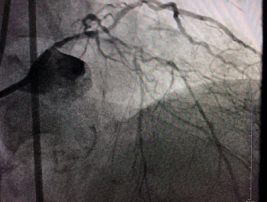

????入院后,經(jīng)冠脈造影術(shù)檢查顯示,陳大爺?shù)淖笾鞲杉叭Т笱埽ㄇ敖抵А⒒匦?、右冠狀動脈)都發(fā)生了彌漫性病變,尤其是左冠狀動脈前降支、回旋支伴隨著嚴(yán)重的鈣化病變,最狹窄處堵塞達(dá)到95%;右冠狀動脈也存在嚴(yán)重鈣化病變,鈣化物幾乎將整個(gè)血管堵滿,導(dǎo)致心肌缺血出現(xiàn)胸悶胸痛癥狀。

術(shù)前

術(shù)前,介入專家首先對陳大爺進(jìn)行了冠脈血管內(nèi)超聲檢查,明確血管內(nèi)結(jié)構(gòu)以及鈣化病變位置和嚴(yán)重程度。然后將帶有鉆石顆粒的高速旋磨頭送入患者血管內(nèi)的鈣化部位,在醫(yī)生的精細(xì)操作下,位于血管內(nèi)的磨頭便以每分鐘10多萬次的轉(zhuǎn)速開始高速旋轉(zhuǎn),根據(jù)“差異性切割”(即只針對嚴(yán)重鈣化和纖維化的病變斑塊組織而不損傷正常組織)原理,將阻塞血管的動脈斑塊迅速磨成極其微小的顆粒,隨血液循環(huán)至血管遠(yuǎn)端并通過毛細(xì)血管床吸收。經(jīng)過幾次旋磨后,阻塞血管腔的鈣化斑塊被逐漸消除,在進(jìn)行球囊擴(kuò)張之后,在兩支血管內(nèi)順利植入四枚支架,成功開通血管,手術(shù)時(shí)間總共用時(shí)1個(gè)多小時(shí)。

術(shù)后